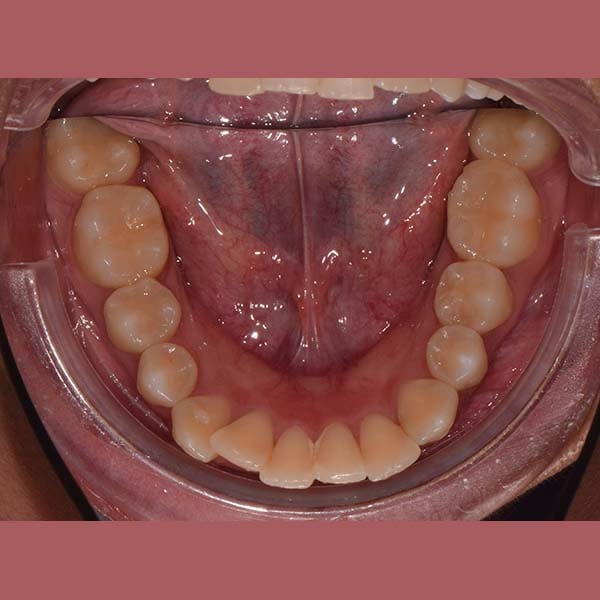

راجعتني هذه الآنسة الشابة وهي تشكو من بروز أسنانها الأمامية في كلا الفكين العلوي والسفلي، وهي حالة نسميها عادةً “البروز المضاعف”.

بعد الفحص، أكد الدكتور خالد الكاتب أن البروز كان كبيراً، وفي معظم هذه الحالات، يكون الحل الأمثل هو قلع بعض الأسنان لتوفير مسافة. وبالفعل، اعتمدت خطة العلاج على قلع الضواحك العلوية والسفلية. تم بعد ذلك استخدام تقويم الأسنان لاستغلال هذه الفراغات في إرجاع الأسنان الأمامية للخلف وتعديل ميلانها.

كما تظهر الصور، تم تصحيح البروز المضاعف بشكل كامل. تراجعت الأسنان الأمامية في كلا الفكين إلى وضعها المثالي، مما أدى إلى تحسين كبير في المظهر الجانبي للوجه وابتسامة أكثر جمالاً وتوازناً. في النهاية، بات بإمكان مراجعتنا الابتسام بثقة مجدداً.